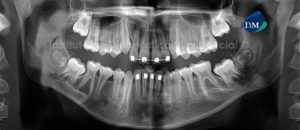

Paciente de sexo masculino de 45 años se acerca al Instituto de Diagnóstico Maxilofacial para evaluación integral por motivos de colocación de implantes. A la